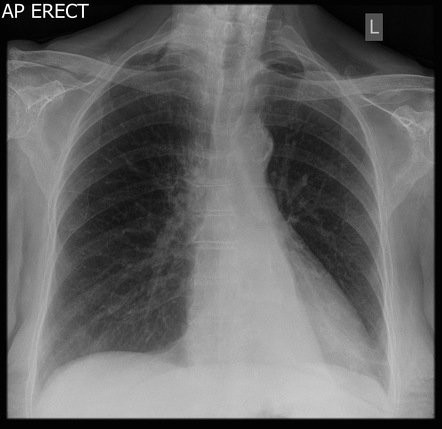

What is going on in this radiograph?

This patient had a left pneumonectomy!

The left lung is gone, and the trachea and heart have moved over to fill the void.